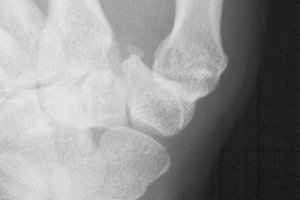

Bilateral hand involvement is common, although the most painful thumb may not be the one with the worst Xray.